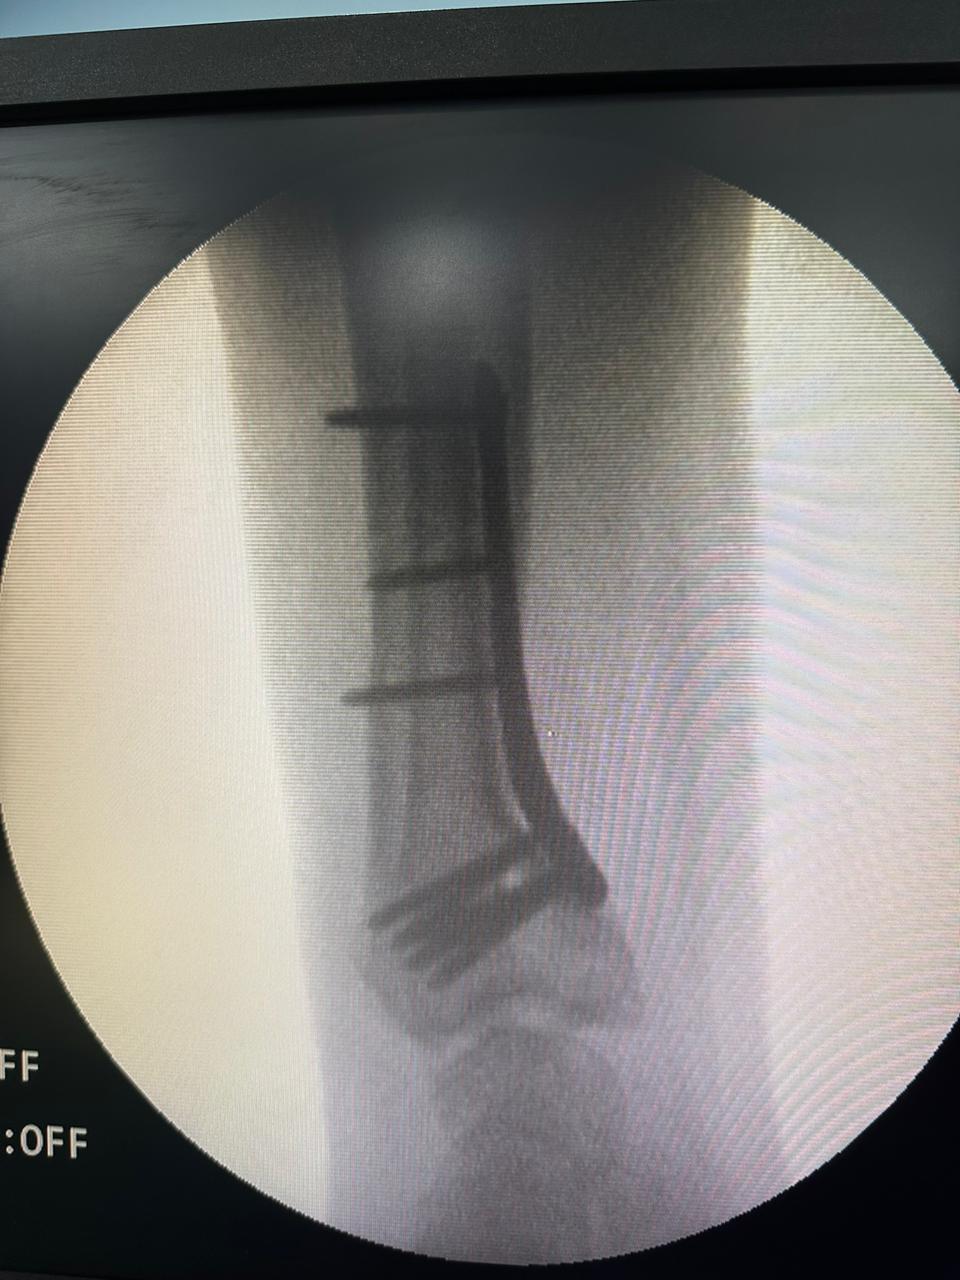

Moments That Mark Meaningful Recovery

Witness real patient transformations at The Ortho Clinic through images that reflect successful treatments and restored mobility.